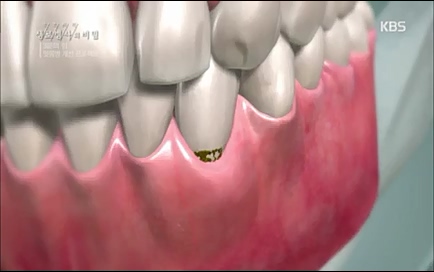

설양조 서울대치과병원. 손을 치아에 비유하고 옷깃이 잇몸이라고 본다면